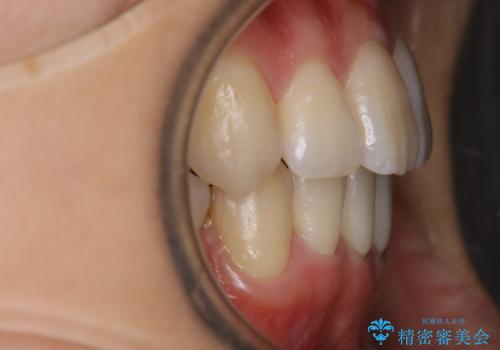

八重歯がスッキリ 抜歯ワイヤー矯正

- 以前からコンプレックスだった八重歯の治療を主訴にご来院されました。

奥歯の上下のズレ等は軽度で、必要なスペースと抜歯により作られるスペースがほぼ等量だったため治療の単純化が計れ、大きな移動・見た目の劇的な変化に対して比較的早期での治療完了となりました。

叢生の度合いが重く、抜歯が必要なケース。八重歯の部分以外には大きな問題は認められなかったため、劇的変化が起こる治療でも比較的短期間で終了することができました。